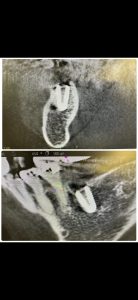

朝からオペだが、10分ちょいで埋入終わり

簡単だから

計測値もグッド👍

6w後には、スキャン印象に仮歯